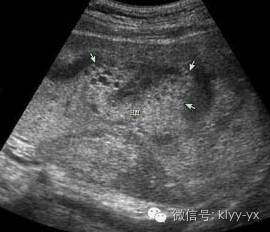

正常怀孕时,胎盘是附着在子宫壁的前、后壁或底部,如果胎盘附着于子宫的部位过低,遮盖子宫颈内口,阻塞了胎儿先露部,即称为前置胎盘。

由于子宫会随着怀孕周数增加而变大,胎盘位置会随之向上提升。因此,如果在孕8个月之后,仍有完全性或是部分性前置胎盘,就会大幅度增加阴道出血的概率。